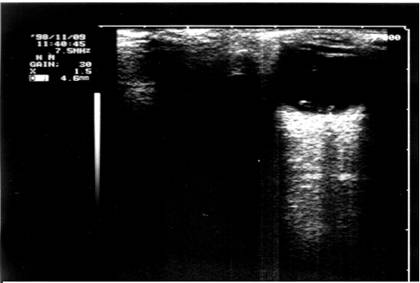

Imaginea ecografica a corpului strain

(localizat in polul posterior al globului, la 3 mm de retina)

- examinarea ecografica realizata in ecografie tip A sau B, determina o localizare de precizie a corpului strain daca acesta are dimensiuni mai mari de 0,75mm (vezi plansa)